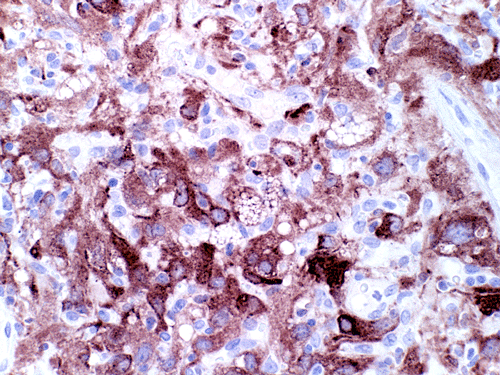

The mass consists of a mixture of spindle cells and clear cells. There is a rich vascular network (Panel A) with sinsusoidal dilatation but no anastomosis of the vascular channels. The endothelial cells appear lean and not protruding into the vascular channel. The clear cells appear to have foamy cytoplasm (̃ in Panel B). The nuclei are hyperchromatic and may appear slighly grooved or lobuated. On immunohistochemistry, the foamy cells are strongly reactive for inhibin (Panel C). These cells are also reactive for S100 protein (Panel D) and neural specific enolase (Panel E) . No immunoreactivity for epithelial membrane antigen (EMA) is observed (Panel F). The tumor is not immunoreactive for cytokeratin.

The truely helpful immunohistochemical marker in this case is inhibin. S100 protein, neural specific enolase, and EMA are rather non-specific.

Microscopically, hemangioblastomas consist of foamy to clear stromal cells interspersed with endothelium lined vascular channels. Clear vacuoles within the stromal cells can be stained with Oil red-O or similar stain if applied to frozen sections. The stromal cells stain strongly for epidermal growth factor receptor (EGFR) and platelet-derived growth receptor factor alpha (PDGF-alpha) 12 and inhibin 13. The stromal cells are typically negative for epithelial membrane antigen (EMA) and cytokeratin 14. In a small number of cases, the stromal cells express glial fibrillary acidic protein (GFAP) 7, 14 and S100 protein 14. These staining results should be interpreted with case as they may represent entrapped glial cells. The admixed capillaries will stain for with typical endothelial markers (Factor-VIII and others) 15, but the stromal cells are typically negative for the endothelial markers. To this date, the pathogenesis and cell origin of hemangioblastomas is not certain.

The primary entity that must be ruled out is metastatic renal cell carcinoma as it can have a similar histologic appearance on H&E and has a similar incidence in patients with von Hippel-Lindau syndrome as that of hemangioblastoma. On hematoxylin-eosin stained sections, renal cell carcinoma can have necrosis, mitosis and large nucleoli, features almost always absent on hemangioblastoma. However, it must also be noted that metastatic renal cell carcinoma can appear rather bland and with out significant atypia. Renal cell carcinoma is also immunoreactive for cytokeratin, CD10, and EMA, while hemangioblastoma is positive for inhibin 13, but negative for cytokeratin, CD10, and EMA.